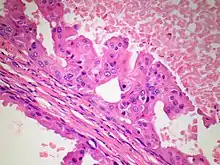

The microscopic histopathology of PACB tumors prepared with hematoxylin and eosin staining shows that >90% of the tumors consist of apocrine gland-like tissue. The lesions must also show that tumor cells have broken through their ducts of origin to invade adjacent tissue in at least one area. Most of the tumor cells (termed type A cells[15]) typically appear somewhat more irregular than normal apocrine gland cells. They have abundant eosinophilic (i.e. pink due to the uptake of the eosin dye) cytoplasm which contain numerous granules[11] and large mitochondria.[15] Their nuclei are large, variably sized and shaped, have multiple nucleoli (which are eosinophilic[11] and may be distinctively large in size[14]), and are surrounded by highly visible nuclear membranes. The cells are arranged into solid sheets, nests, papillae, and/or cords (see Figs. 1 and 2).[11] The tumor cells' cytoplasmic granules test positive when treated with the PAS diastase stain.[16] Binucleated cells, i.e. cells with two nuclei, are common.[10] Less commonly, type B apocrine cells are present; these cells have a more foamy and vacuolated cytoplasm (i.e. containing multiple vacuoles) than type A cells[15] and often resemble foamy histiocytes or sebaceous gland cells.[17] The tumor cells have low to moderate rates of proliferation based on their Ki-67 protein levels.[7] PACB tissues may have localized areas that contain mucin-like secretions within their luminal ducts,[10] localized areas of necrosis (i.e. foci containing dead or dying cells), and/or microcalcifications spotted throughout the apocrine tissue.[11] The stroma (i.e. connective tissue between the sheets, nests, papilla and cords of cells) typically contains non-malignant, infiltrating lymphocytes (see Fig. 3). In an examination of 41 PABC tumors, 33 (80.5%) had <50% of their stroma tissues infiltrated with these cells while 8 (19.5%) had ≥50% of their stroma tissues infiltrated with them. Tumors with ≥50% of their stroma infiltrated with lymphocytes tended to have carcinoma cells that had high rates of proliferation.[11] Metastatic and recurrent PACB tumors have a histopathology similar to their original primary tumors.[14]

Non-invasive apocrine carcinoma of the breast, i.e. apocrine carcinoma in situ, is classified as a variant of the ductal carcinoma in situ tumors of the breast; it is therefore termed apocrine ductal carcinoma in situ (ADCIS).[9] ADCIS tumors have appreciable areas with apocrine tissue-like histopathology, i.e. areas composed of apocrine cells that have, to varying extents, the abnormal cytoplasmic, nuclear, and nucleolar features found in PACB (see Fig 4). Unlike PACB, the apocrine carcinoma cells in ADCIS have by definition not spread beyond their ducts of origin to invade nearby non-ductal tissue and have not metastasized to local lymph nodes or distant tissues.[4] While there is no consensus on the criteria used for its diagnosis, ADCIS is most often defined as a non-invasive breast tumor consisting of lactiferous ducts that are filled with neoplastic apocrine cells;[4] the cells in these tumors, similar to those in PACB, are estrogen receptor-negative, progesterone-receptor negative, and, in at least 10% of these cells, androgen receptor-positive.[9] Some studies have classified ADCIS as low, intermediate, or high nuclear grade based on how closely the nuclei of their tumor's apocrine cells resemble the nuclei of normal breast cells. In general, high nuclear grade tumor cells have more abnormal nuclei and indicate that this tumor is more aggressive than a lower grade tumor. Low- and intermediate-grade ADCIS tumors may be misdiagnosed as non-cancerous lesions (e.g. as atypical apocrine metaplasia or atypical apocrine hyperplasia) because of their more benign microscopic appearance.[4] ADCIS tumors often have architectural patterns consisting of cribriform (riddled with small holes), micropapillary (thin finger-like growths) and/or solid growth (i.e. do not contain cysts or liquid areas),[4] sites with necrosis, and/or sites with microcalcifications; while these microscopic findings are more common in high nuclear grade ADCIS, their presence supports the diagnosis of ADCIS in low and intermediate tumors.[9] Some authors have proposed that in situ ductal tumors with apocrine histopathology should be larger than 0.2 centimeters in order to be diagnosed as ADCIS.[4][9]